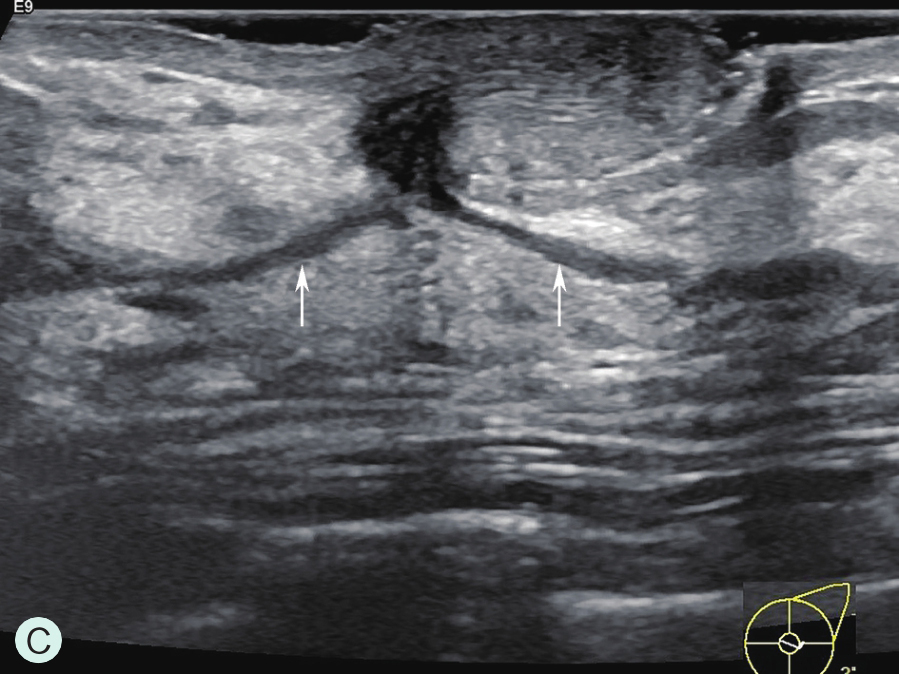

乳管系统为一由输乳管反复分支而呈现树状分支的结构单位,90%以上为2分支型,多分支型最多可达6分支,导管直径一般为2.0~4.5mm,随着导管分支逐渐变细。每个乳腺由15~20个腺小叶导管系统构成(图1-2-1A、图1-2-1B),每个系统组成一个乳腺叶,每个腺叶有其相应的导管系统,每个腺叶以乳头为中心呈轮辐样放射排列,各有一个导管向乳头引流,称输乳管(图1-2-1A),在乳头的基底部,距乳头开口约0.5cm处呈壶腹样膨大(图1-2-1C~图1-2-1E),口径为5~6mm,充满乳汁直径可达6~8mm,供暂时储存乳汁,该膨大区称乳窦。窦外末段输入管口径又缩小,并开口于乳头。从乳管开口到壶腹部的一段导管内衬以多层鳞状上皮细胞,以下的中小导管及腺泡内衬单层柱状细胞。若单个导管内的上皮细胞增殖呈乳头状突入管腔,称为导管内乳头状瘤。乳腺癌主要来源于腺管的柱状上皮细胞,发生于腺泡的癌仅占5%。

图1-2-1 乳腺结构与影像图

A.乳腺模式图;B.乳腺小叶声像图;C、D.乳腺导管声像图;E.乳腺扩张导管MRI图